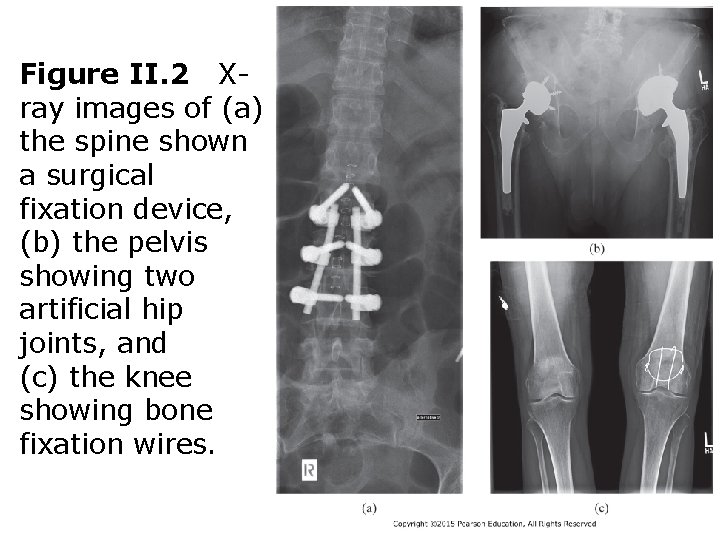

Figure II. 2 Xray images of (a) the spine shown a surgical fixation device, (b) the pelvis showing two artificial hip joints, and (c) the knee showing bone fixation wires.